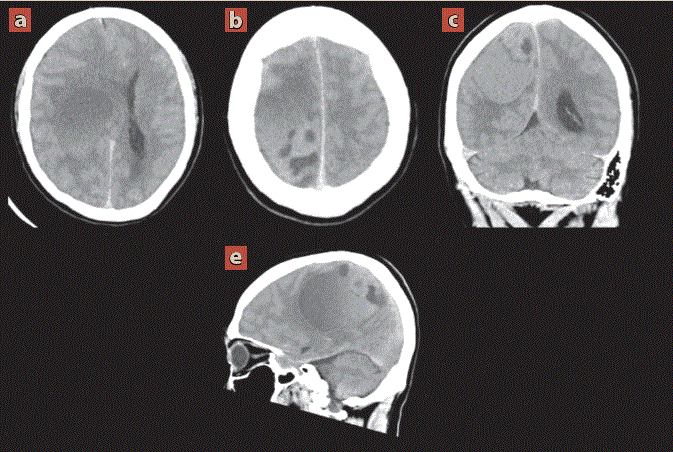

Fue valorado por el servicio de neurocirugía, quienes en la exploración neurológica encontraron funciones mentales conservadas, con disminución marcada de la fuerza muscular del hemicuerpo izquierdo, por lo que se solicitó tomografía de cráneo como abordaje diagnóstico inicial (figura 1).

Imagen: Díaz Escareño et al.

Cortes axiales (a, b) con reconstrucciones multiplanares coronal (c) y sagital (d). Se aprecia lesión aparentemente extraaxial frontoparietal derecha, ovalada, heterogénea de predominio hipodenso (20 UH) al parenquima cerebral con dimensiones de 87 x 62 x 50 mm en sus eje longitudinal, anteroposterior y transverso respectivamente, que condiciona efecto de masa sobre el cuerpo calloso, núcleos de la base y talamo ipsilateral con desplazamiento de la línea media de hasta 20 mm.

Figura 1 Tomografía computarizada de cráneo simple